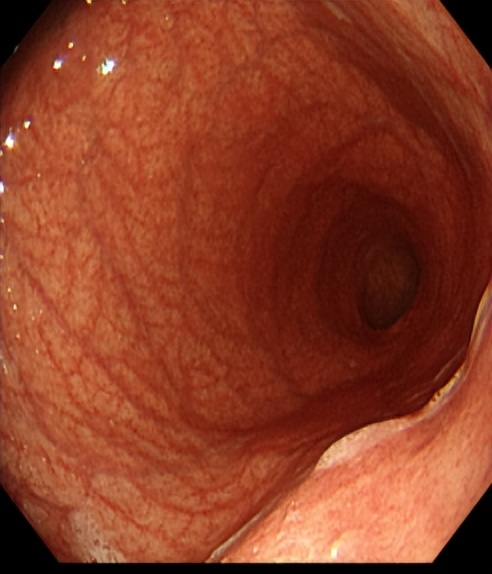

所谓A型胃炎是慢性胃炎的一种特殊类型,它的另外一个学名是自身免疫性胃炎。自身免疫性胃炎的特点是免疫介导的胃体壁细胞被破坏,引起胃酸分泌减少,进而影响维生素B12、铁吸收等,导致恶性贫血(巨幼红细胞性贫血)、缺铁性贫血等。形态学上,是以胃体为主的萎缩性胃炎,胃窦部未见萎缩或轻度萎缩,即所谓的逆萎缩现象;它与幽门螺杆菌感染引起的胃窦萎缩,继而向胃体部扩展的萎缩性胃炎形态表现不同。

自身免疫性胃炎胃镜下表现-胃体萎缩

(图片源于网络)